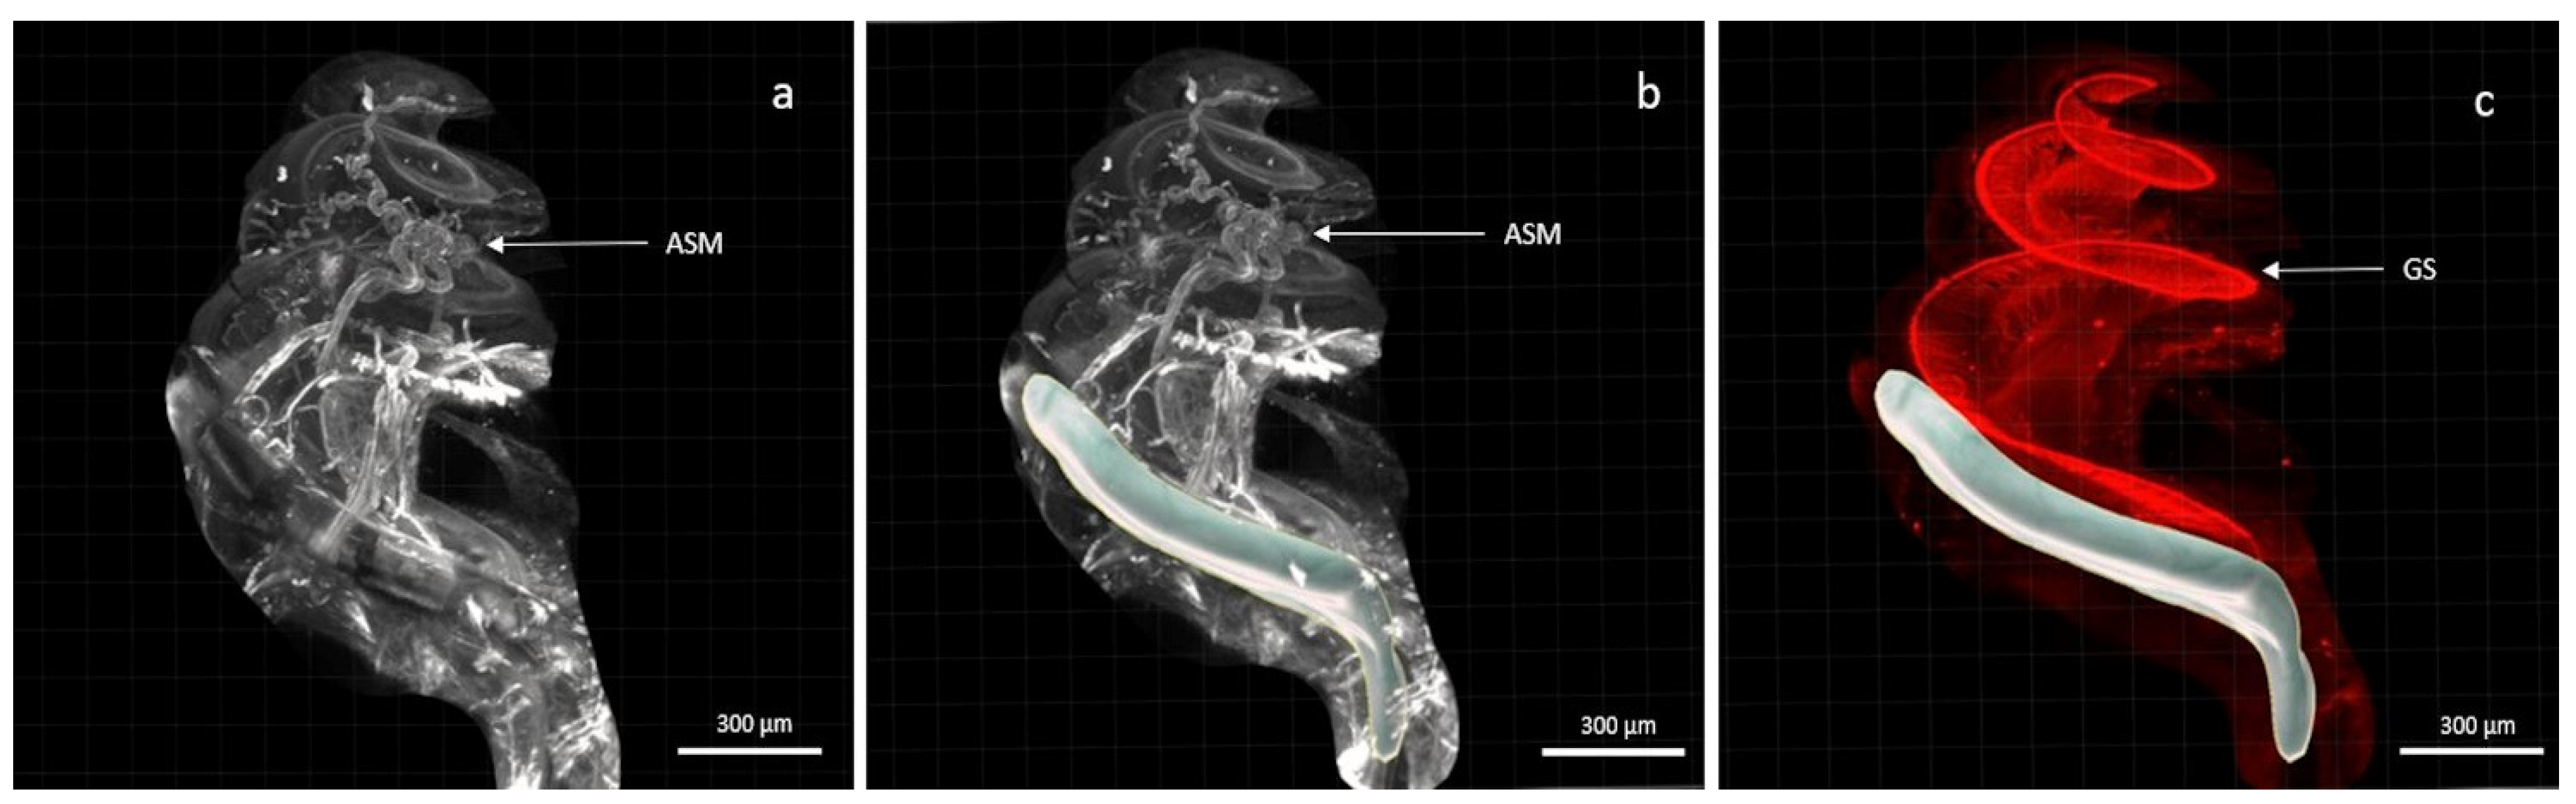

2.4. Light-Sheet Microscopy

2.5. Three-Dimensional (3D) Analysis

3. Results